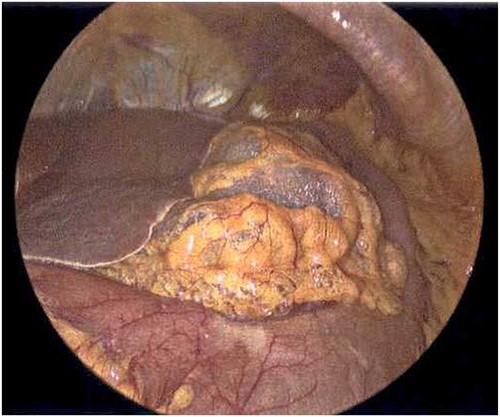

On Hospital Day 2, an interval CXR showed continued resolution of the right-sided pneumothorax but worsening subcutaneous emphysema of the bilateral chest wall and pneumoperitoneum (Fig. 3). Surgical consultation was sought, leading to diagnostic laparoscopy. In the abdomen, emphysematous changes within the gastrohepatic ligament and omental adhesions to the anterior abdominal wall were visualized (Figs 5 and 6). Laparoscopic exploration revealed no diaphragmatic injury or perforated viscera but identified emphysematous changes throughout the preperitoneal space, small and large bowel mesentery, and right paracolic gutter (Figs 7 and 8). Immediate post-op CXR no longer showed evidence of pneumoperitoneum (Fig. 4). The patient was transferred back to the ICU and extubated after three days on Day 5. After the removal of chest tube and transfer to a medical floor on Day 8, the patient developed aspiration pneumonia that was treated with antibiotics. She was discharged on Day 15.

Laparoscope of the right paracolic gutter revealing emphysematous changes of the mesentery.